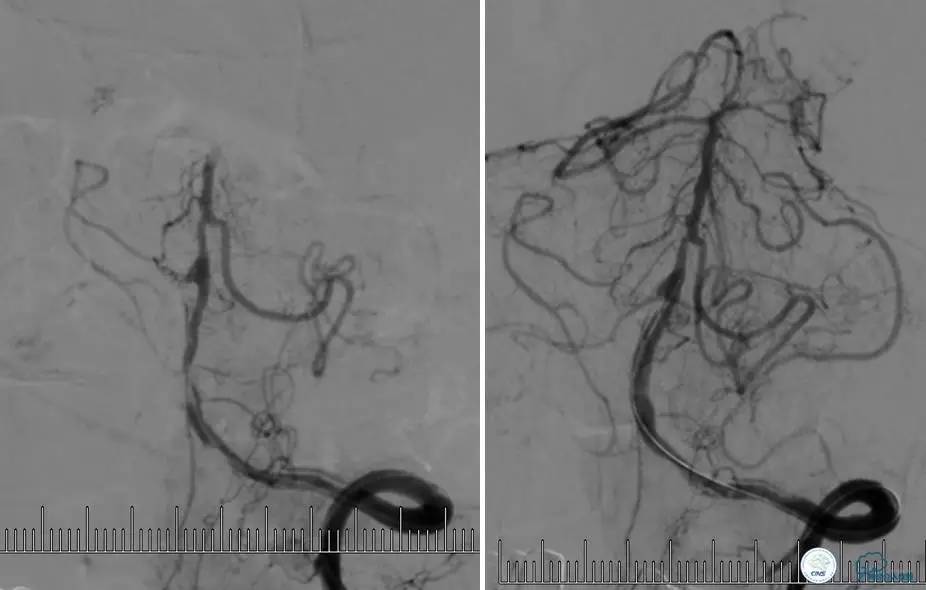

病例6

患者:49岁女性,脑梗死30天。

左侧颈内动脉末端闭塞,末端圆钝且有一定成角,开通难度较大,多次尝试导丝才成功穿过闭塞段。

开通效果很满意,术后症状明显恢复。

病例7

患者:反复发作右侧肢体无力、言语不清15天。

导丝很容易通过闭塞段。

顺利置入Wingspan支架,成功开通,手术顺利。